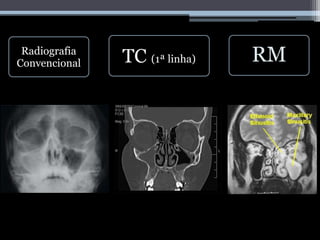

TC

(1ª linha)

Detalhes anatómicos e

ósseos

Visualização de variações

anatómicas

Deteção de processos

erosivos e deficiências

adquiridas ósseas

Deteção de patologias

RM

Melhor resolução de tecidos

moles

Importante quando a doença

sino-nasal se alastra para o

seio cavernoso e

compartimento intracraniano

Através das janelas T1 e T2

distinguir entre as diferentes

patologias

Sequências T1 e T2 ‘fat-

supressed’, para visualização

de extravasamento

extrasinusal da doença

Radiografia

Convencional TC (1ª linha) RM

• #9 Tumores não são hiperdensos, por isso por TAC consegue-se distinguir. A TAC capta, mas a RM distingue. As variações anatómicas são importantes para uma cirurgia endoscópica, uma vez que o cirurgião pode perfurar equivocamente romper artérias, causando hemorragia. Se a extensão da sinusite for intra-orbital, conseguimos ver por TAC. Através das janelas T1 e T2, e a partir das percentagens proteicas, podemos distinguir entre sangue, fungos e secreções (quando é hiperintenso). - Método auxiliar mais antigo no diagnóstico de rinossinusites (opacificação ou velamento do interior da cavidade paranasal, níveis hidroaeres ou espessamento muscoso superior a 6-8 mm – para crianças e adultos respectivamente) -Barato (em muitas situações pode ser o método de diagnostico complementar único disponível, como no brasil- condições precárias); -Rápido; -Técnica limitada (pouca qualidade de imagem). Raio x – direita e TAC a surgir depois á esquerda.

• #10 The real value of unenhanced CT is the following: if you see an opacified sinus with hyperdense contents, it is usually a sign of benign disease. Tumor is not hyper-dense.  The hyperdensity is due to one or a combination of the following: inspissated secretions fungus blood